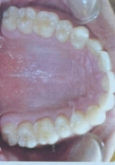

Ur such a cutie patootieSo I just got X-rays and pictures of my teeth from my ortho. I was wondering if someone can look at them and advise me on what I should do to get straight teeth, a wide palate, even bite, and forward growth/ccw rotation

Moneyball thanks broView attachment 4263276

i use my eyes and look, this is wide, there is no crowding etc, only in your lower teeth there is a bit of crowding wich braces will fix